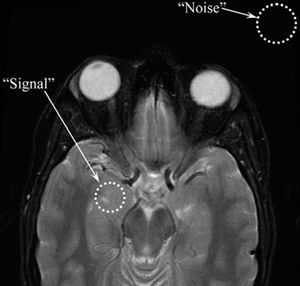

Measurement of signal-to-noise ratio (SNR) from an image acquired with a single receiver coil and no parallel imaging acceleration is determined from the ratio of the average signal in the “Signal” ROI and the standard deviation of the noise in the “Noise” ROI, placed outside the object. This approach assumes that noise is uniform across the image. In addition, a correction factor for the underestimation of noise must be made.